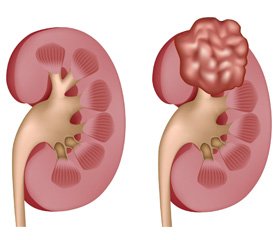

Етіопатогенез нирково-клітинного раку

В огляді літератури висвітлюється проблема раку нирки, що залишається однією з найважливіших в онкології. Багаторічні спостереження за змінами частоти захворювання, стадійності раку, а також тривалості життя хворих дають підставу прогнозувати рівень захворюваності та виживаності хворих на рак нирки. Кількість хворих із місцево поширеним процесом у нирці в Україні становить, за даними літератури, близько 40 %. Викликає інтерес динаміка і причини захворюваності на рак нирки, а оскільки кількість запущених форм залишається високою, то актуальним є визначення шляхів профілактики та ранньої діагностики для своєчасного виявлення та вибору оптимального методу лікування.

В обзоре литературы освещается проблема рака почки, которая остается одной из важнейших в онкологии. Многолетние наблюдения за изменениями частоты заболевания, стадийности рака, а также продолжительности жизни больных дают основание прогнозировать уровень заболеваемости и выживаемости больных раком почки. Количество больных с местно распространенным процессом в почке в Украине составляет, по данным литературы, около 40 %. Представляют интерес динамика и причины заболеваемости раком почки, а так как количество запущенных форм остается высоким, то актуальным является определение путей профилактики и ранней диагностики для своевременного выявления и выбора оптимального метода лечения.

The review of the literature covers the problem of kidney cancer, which remains one the most important in oncology. Long-term monitoring of changes in incidence, staging of cancer, as well as the duration of life of patients give reason to predict morbidity and survival rate in patients with renal kidney cancer. Number of patients with locally advanced process in the kidney in Ukraine is, according to the literature, about 40 %. The dynamics and causes of kidney cancer morbidity are of interest, and since the number of advanced forms remains high, it is urgent to identify ways of prevention and early diagnosis for timely detection and selection of the optimal treatment regimen.

За сучасними даними, нирково-клітинний рак (НКР) являє собою поліетіологічне захворювання [19, 22], на виникнення і розвиток якого можуть вплинути багато абсолютно різних факторів: генетичні, гормональні, хімічні, променеві, імунологічні та інші.

Захворюваність на рак нирки в середньому становить 4 випадки на 100 000 населення. Більше того, відзначається зростання захворюваності на рак нирки, що пояснюється не тільки поліпшенням виявлюваності новоутворень даного органа, а й істинним зростанням захворюваності на нирково-клітинний рак. Рак нирки займає третє місце серед найбільш частих новоутворень сечостатевих органів, при цьому пухлина нирки становить близько 3 % усіх новоутворень дорослої людини. Найбільш поширеним новоутворенням нирки є нирково-клітинний рак (85–90 %).

Морфогенез нирково-клітинного раку включає: розвиток частіше дифузного нефросклерозу; появу у фокусах склерозу передракових змін епітелію у вигляді вогнищевої гіперплазії нефроцитів із виникненням дисплазії, що супроводжується генетичною нестабільністю й пошкодженнями генома епітеліальних клітин; виникнення маленьких епітеліальних пухлин нирок, одні з яких спочатку є нирково-клітинним раком, а інші — аденомами; прогресію пухлини з наростанням гетерогенності пухлинних клонів, що виявляється при дослідженні ДНК.